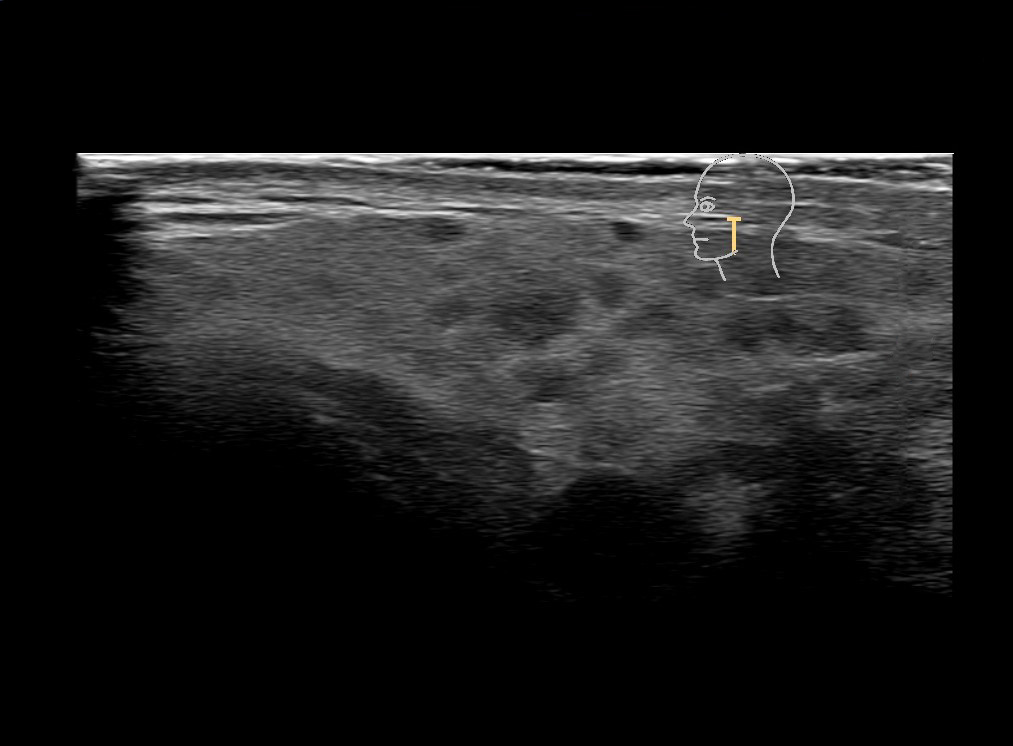

Study the first image to recognize the different layers. If you are sure about the layers, swipe to the second image to view the answer (if applicable).